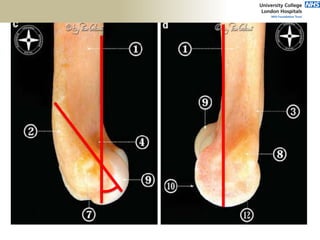

aMCL

• constant valgus load

• Resisted by aMCL

• isometric through ROM

• Valgus load

1. MCL

2. anterior capsule

3. RCj

• tensile strength

261+71N

LUCL

• Resists varus load

- flexion:

Trochlea (75%)

- Extension

LuCL (46%)

• PLRI

233_116N